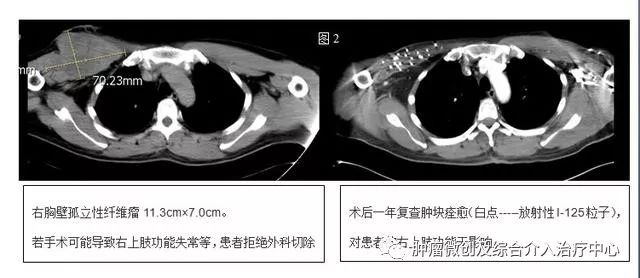

3.胸壁肿瘤碘125粒子植入术。